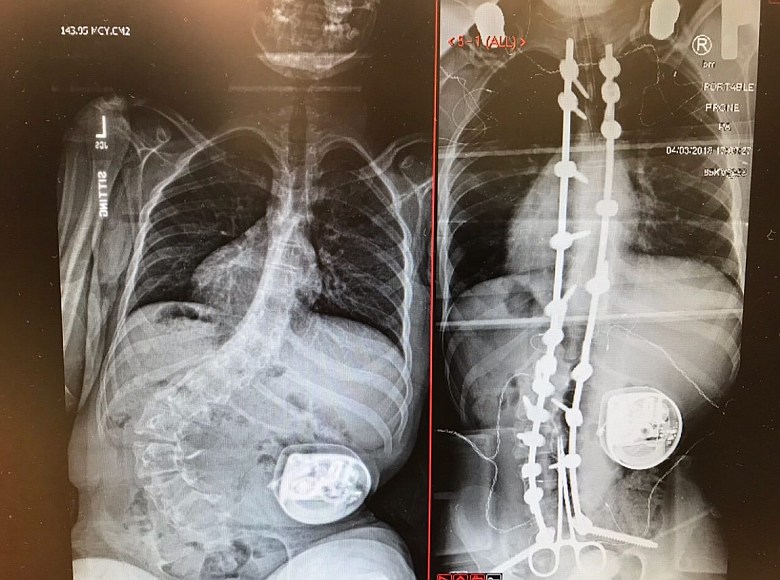

Przed i po operacji skoliozy korekcyjnej